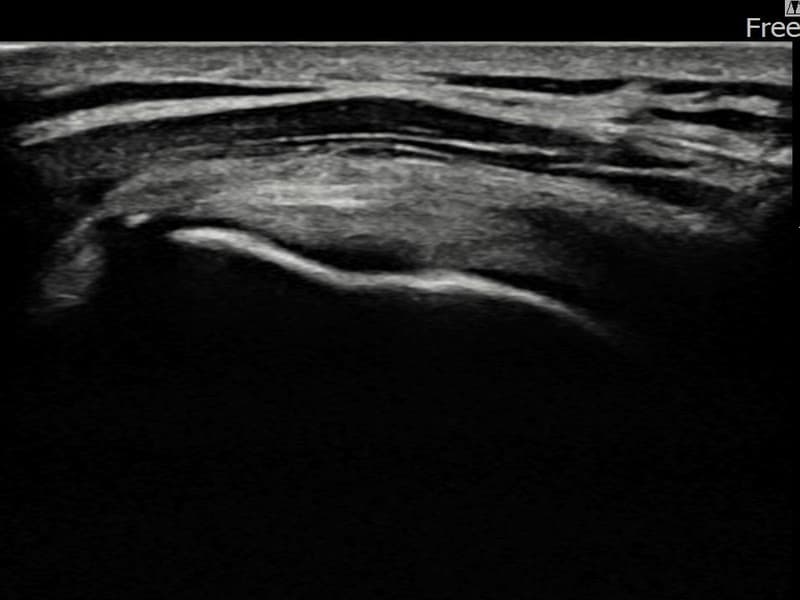

术后

术前超声确认左侧 冈上肌腱 部分撕裂,左侧冈上肌腱回声不连续伴肌腱缺损(7mm × 3mm (肌腱厚度约30%缺损))。术后超声显示撕裂部位充满再生组织,肌腱连续性恢复,回声模式正常化。

该患者持续肩痛。详细超声检查确认左侧 冈上肌腱 部分撕裂(缺损:7mm × 3mm (肌腱厚度约30%缺损))。在超声引导下实施非手术缩小缝合术。术后佩戴支具约4-6周,随后进行分阶段康复锻炼。随访超声确认肌腱连续性恢复、结构稳定,患者顺利回归日常生活。